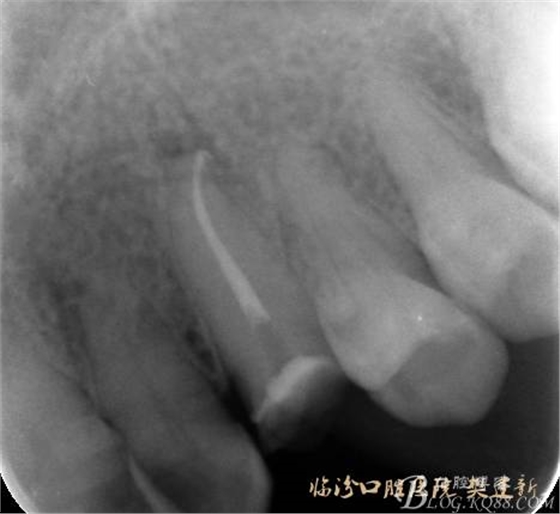

圖3 根管治療后X片